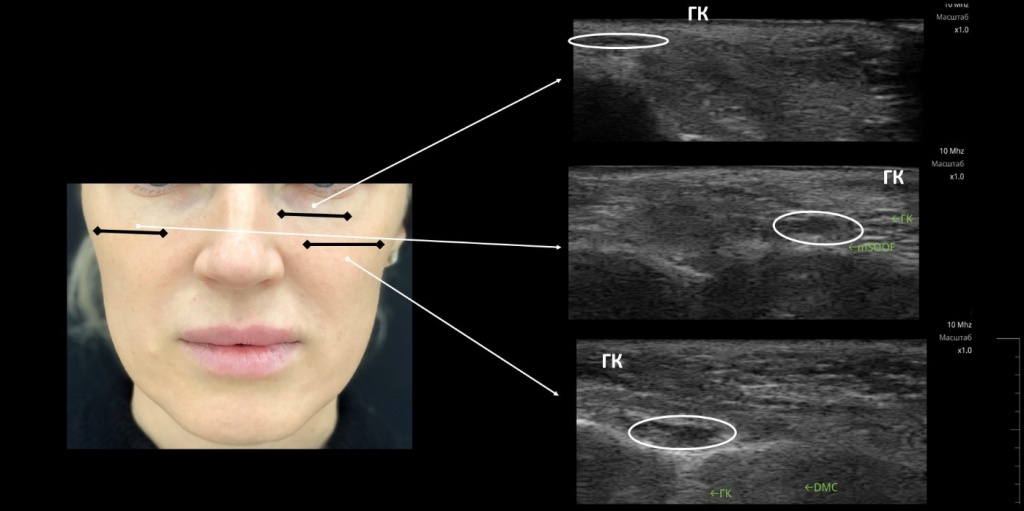

Определение ранее введенных препаратов

Если пациент приходит на консультацию впервые (или возвращается в клинику после длительного перерыва), важно понимать, что в настоящее время находится в мягких тканях его лица. Пациентов, которые обращаются к врачу-косметологу первый раз, особенно после 35–40 лет, крайне мало

Большинство пациентов, пришедших на прием к новому врачу, затрудняется сказать, что было инъецировано им в других клиниках. Это очень значимый момент. Причем если до этого пациент проводил лечение в клинике, то доверия в отношении препарата больше, а если где-то «у Маши», и этот гель находился в тканях в первоначальном объеме более трех лет, то возникает вопрос о природе препарата.

Существуют УЗИ-признаки разных по природе гелей для контурной пластики. Мы не будем останавливаться на них подробно — они детально описаны в литературе.

Рекомендация начинающим свой путь в ультразвуковой диагностике врачам-косметологам: по ходу своей практики собирайте различные «картинки» визуализации, и тогда основные признаки разных гелей будут очень четко видны при использовании разных аппаратов для ультразвуковой диагностики.

На рис. 1 представлено фотоизображение ультразвукового исследования препаратов для контурной пластики, введенных 12 месяцев назад: Teosyal Redensity 2 в области слезной борозды, Teosyal RHA4 в области mSOOF, Teosyal Ultra Deep в области DMC2, 3. При исследовании видны признаки резорбции гелей, в большей степени в области глубоких жировых пакетов средней трети лица, без формирования фиброзной капсулы вокруг геля.